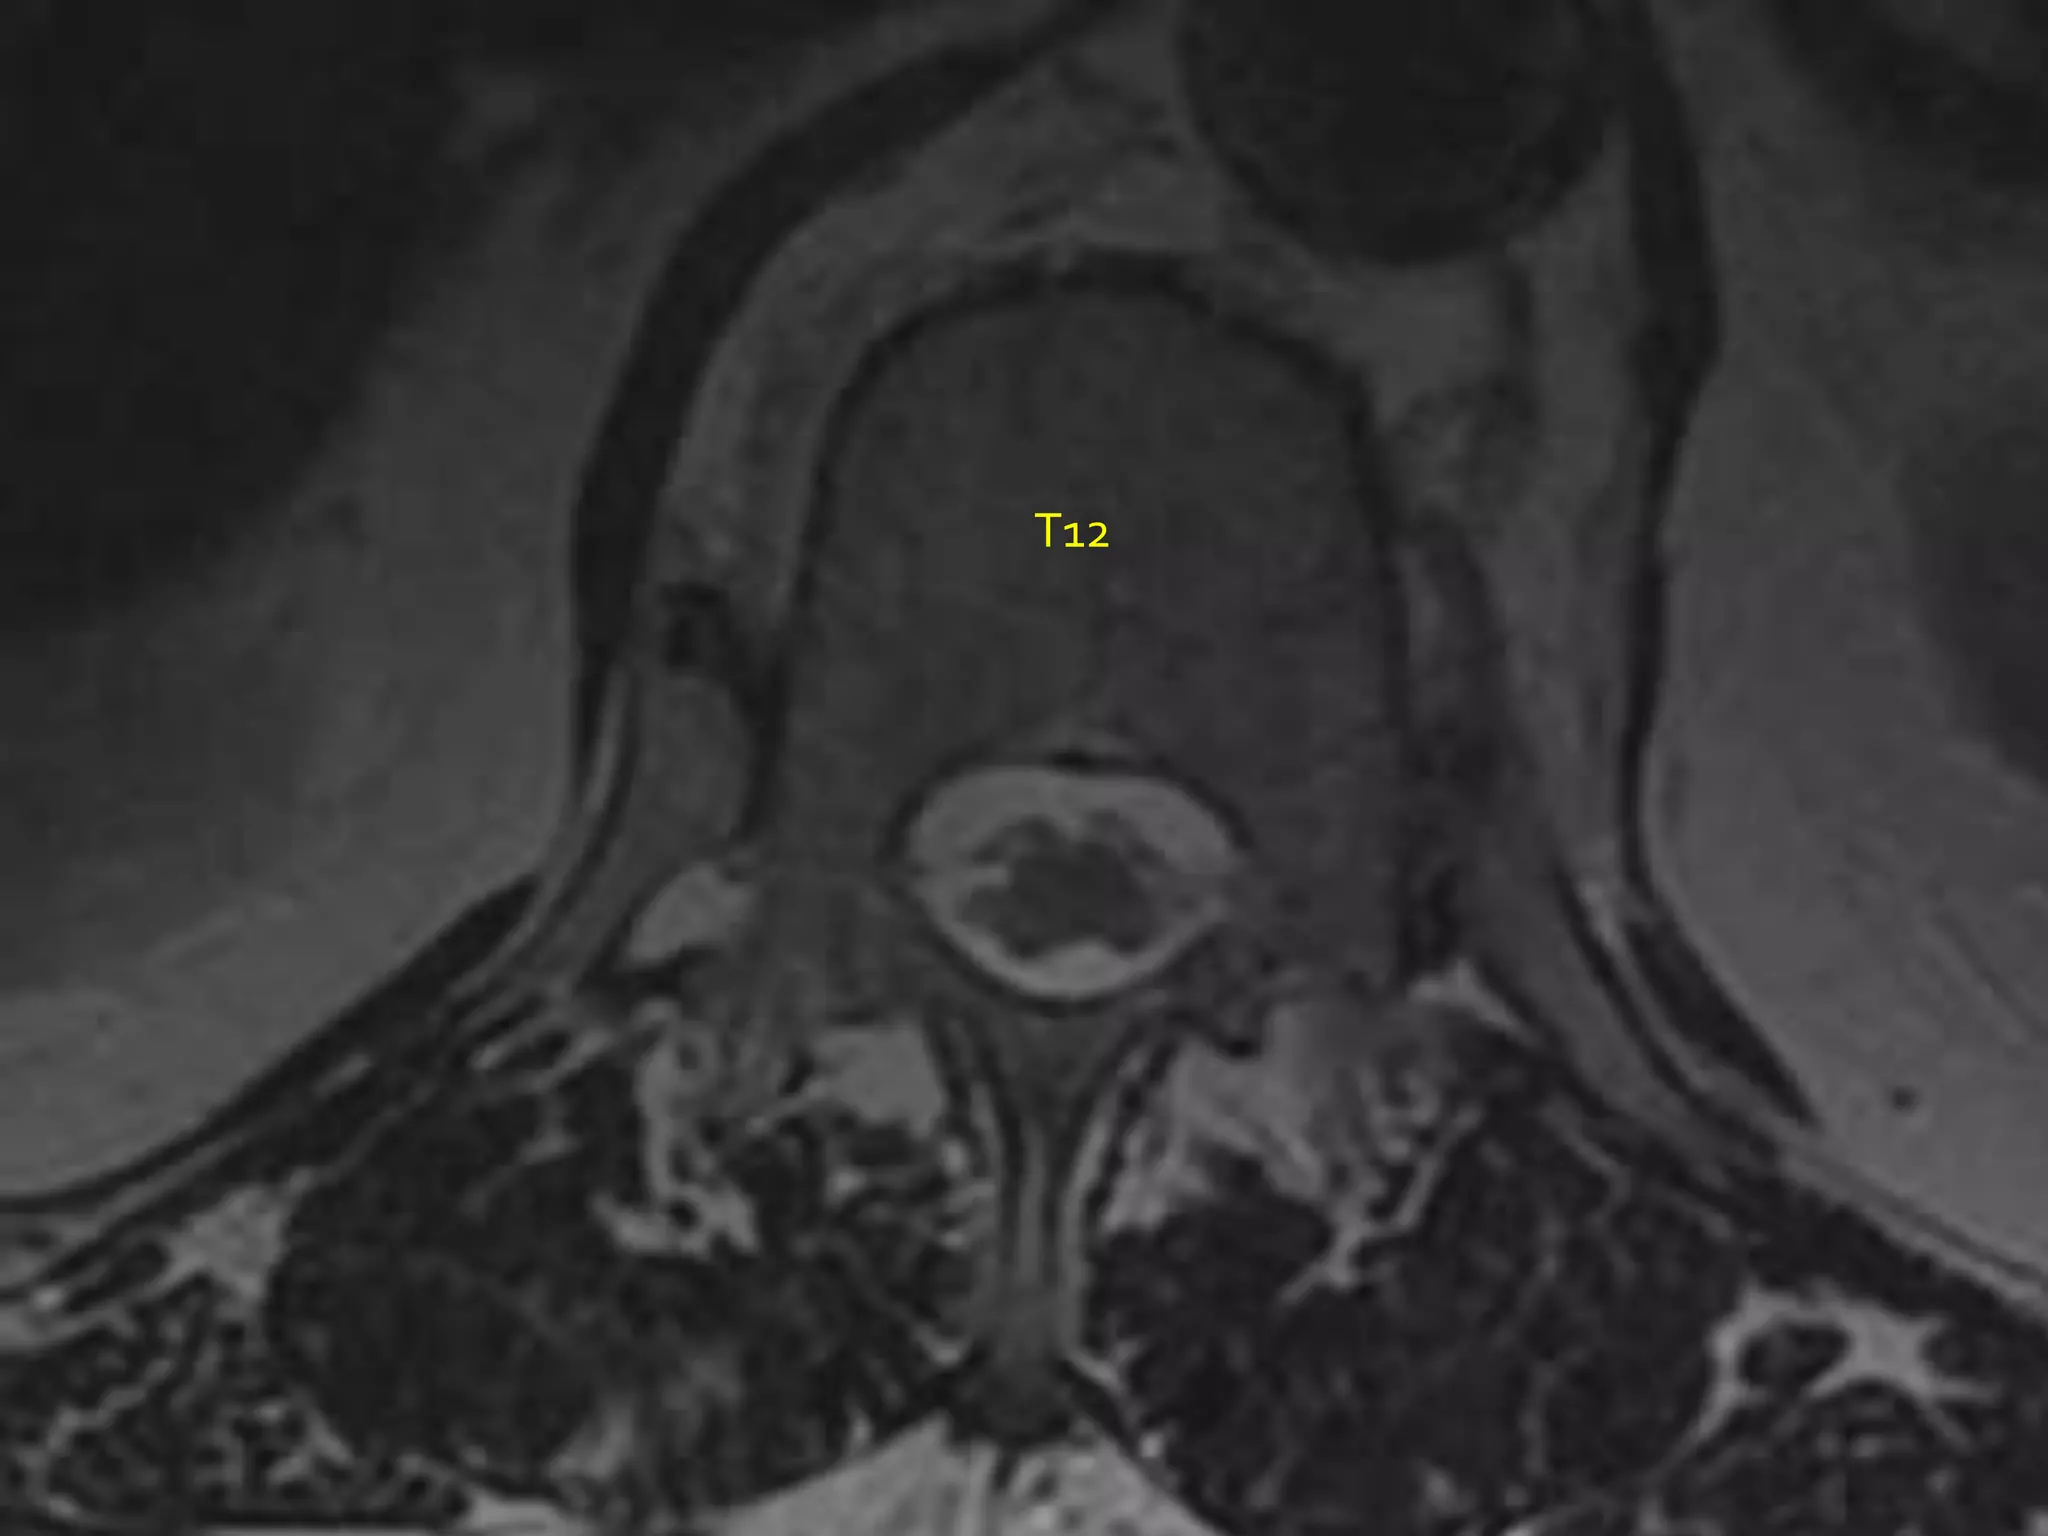

Lumbar Spinal Stenosis ULBD technique | PPTX

Spine Surgery Lecture ULBD | PPTX

ULBD - li-spine.com

Microscopic tubular unilateral laminotomy for bilateral decompression ...

Microscopic ULBD. A Hypertrophied ligamentum flavum and LSS. B ...

Frontiers | A meta-analysis of clinical effects of microscopic ...

Figure 1 from A meta-analysis of clinical effects of microscopic ...

Navigation during the sULBD approach. A Planning incision for left ...

Clinical and radiological data analysis in TE-ULBD cohort. | Download ...

Figure 5 from Clinical Results And Review of Techniques of Lumbar ...

Lumbar endoscopic unilateral laminotomy for bilateral decompression (LE ...

AO Surgery Reference丨显微镜通道下ULBD治疗腰椎管狭窄症_腰椎管狭窄_腰椎管狭窄治疗方式 - 好大夫在线

(PDF) A meta-analysis of clinical effects of microscopic unilateral ...

(PDF) Advantages of New Endoscopic Unilateral Laminectomy for Bilateral ...